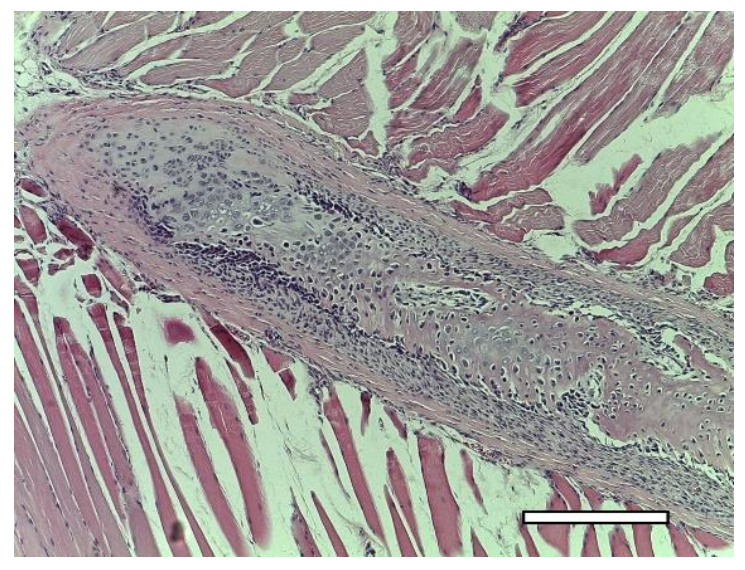

2.5.3. 3rd Group (Collagen + dECM + MSC)